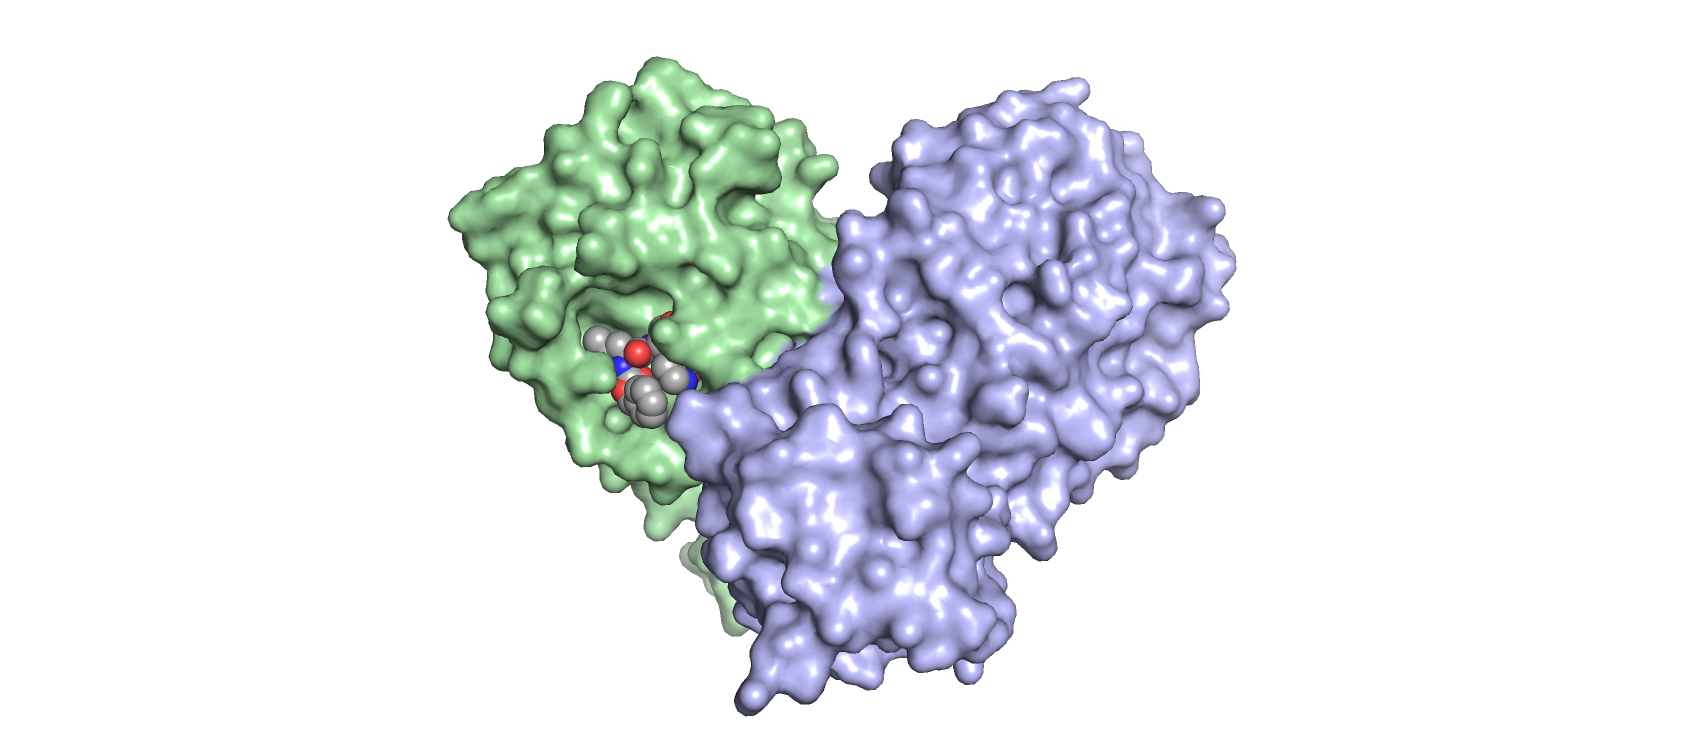

New anti-viral based therapies for Covid-19: Protease inhibitors

Researchers at MWC are looking to develop novel inhibitors for SARS-CoV-2 Mpro by leveraging expertise within MWC’s Infectious Disease network for anti-viral drug development.

Smarter drug design

An advanced experimental technique linked to high powered computation is becoming an increasingly important tool for MWC researchers developing new drugs.